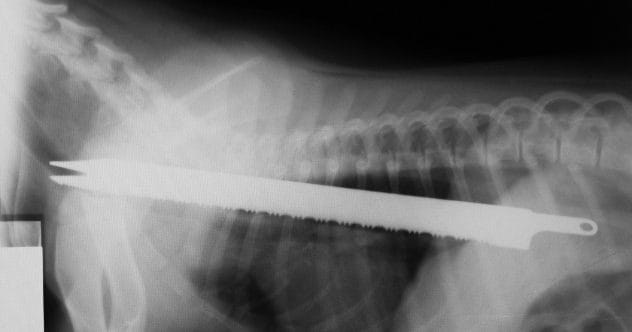

Now we enter the realm of medical malpractice, where surgical tools are unintentionally left inside patients. A surgical retractor is an instrument used to hold organs or tissues aside during an operation, providing surgeons with a clear view.

In a notable case, a man named Donald Church was left with a 12-inch retractor inside his chest after surgery. When he complained of sharp, persistent pain, his surgeon initially dismissed it as normal post-operative discomfort. However, after a month with no improvement, an X-ray revealed the forgotten instrument. This was a serious oversight with painful consequences for the patient.